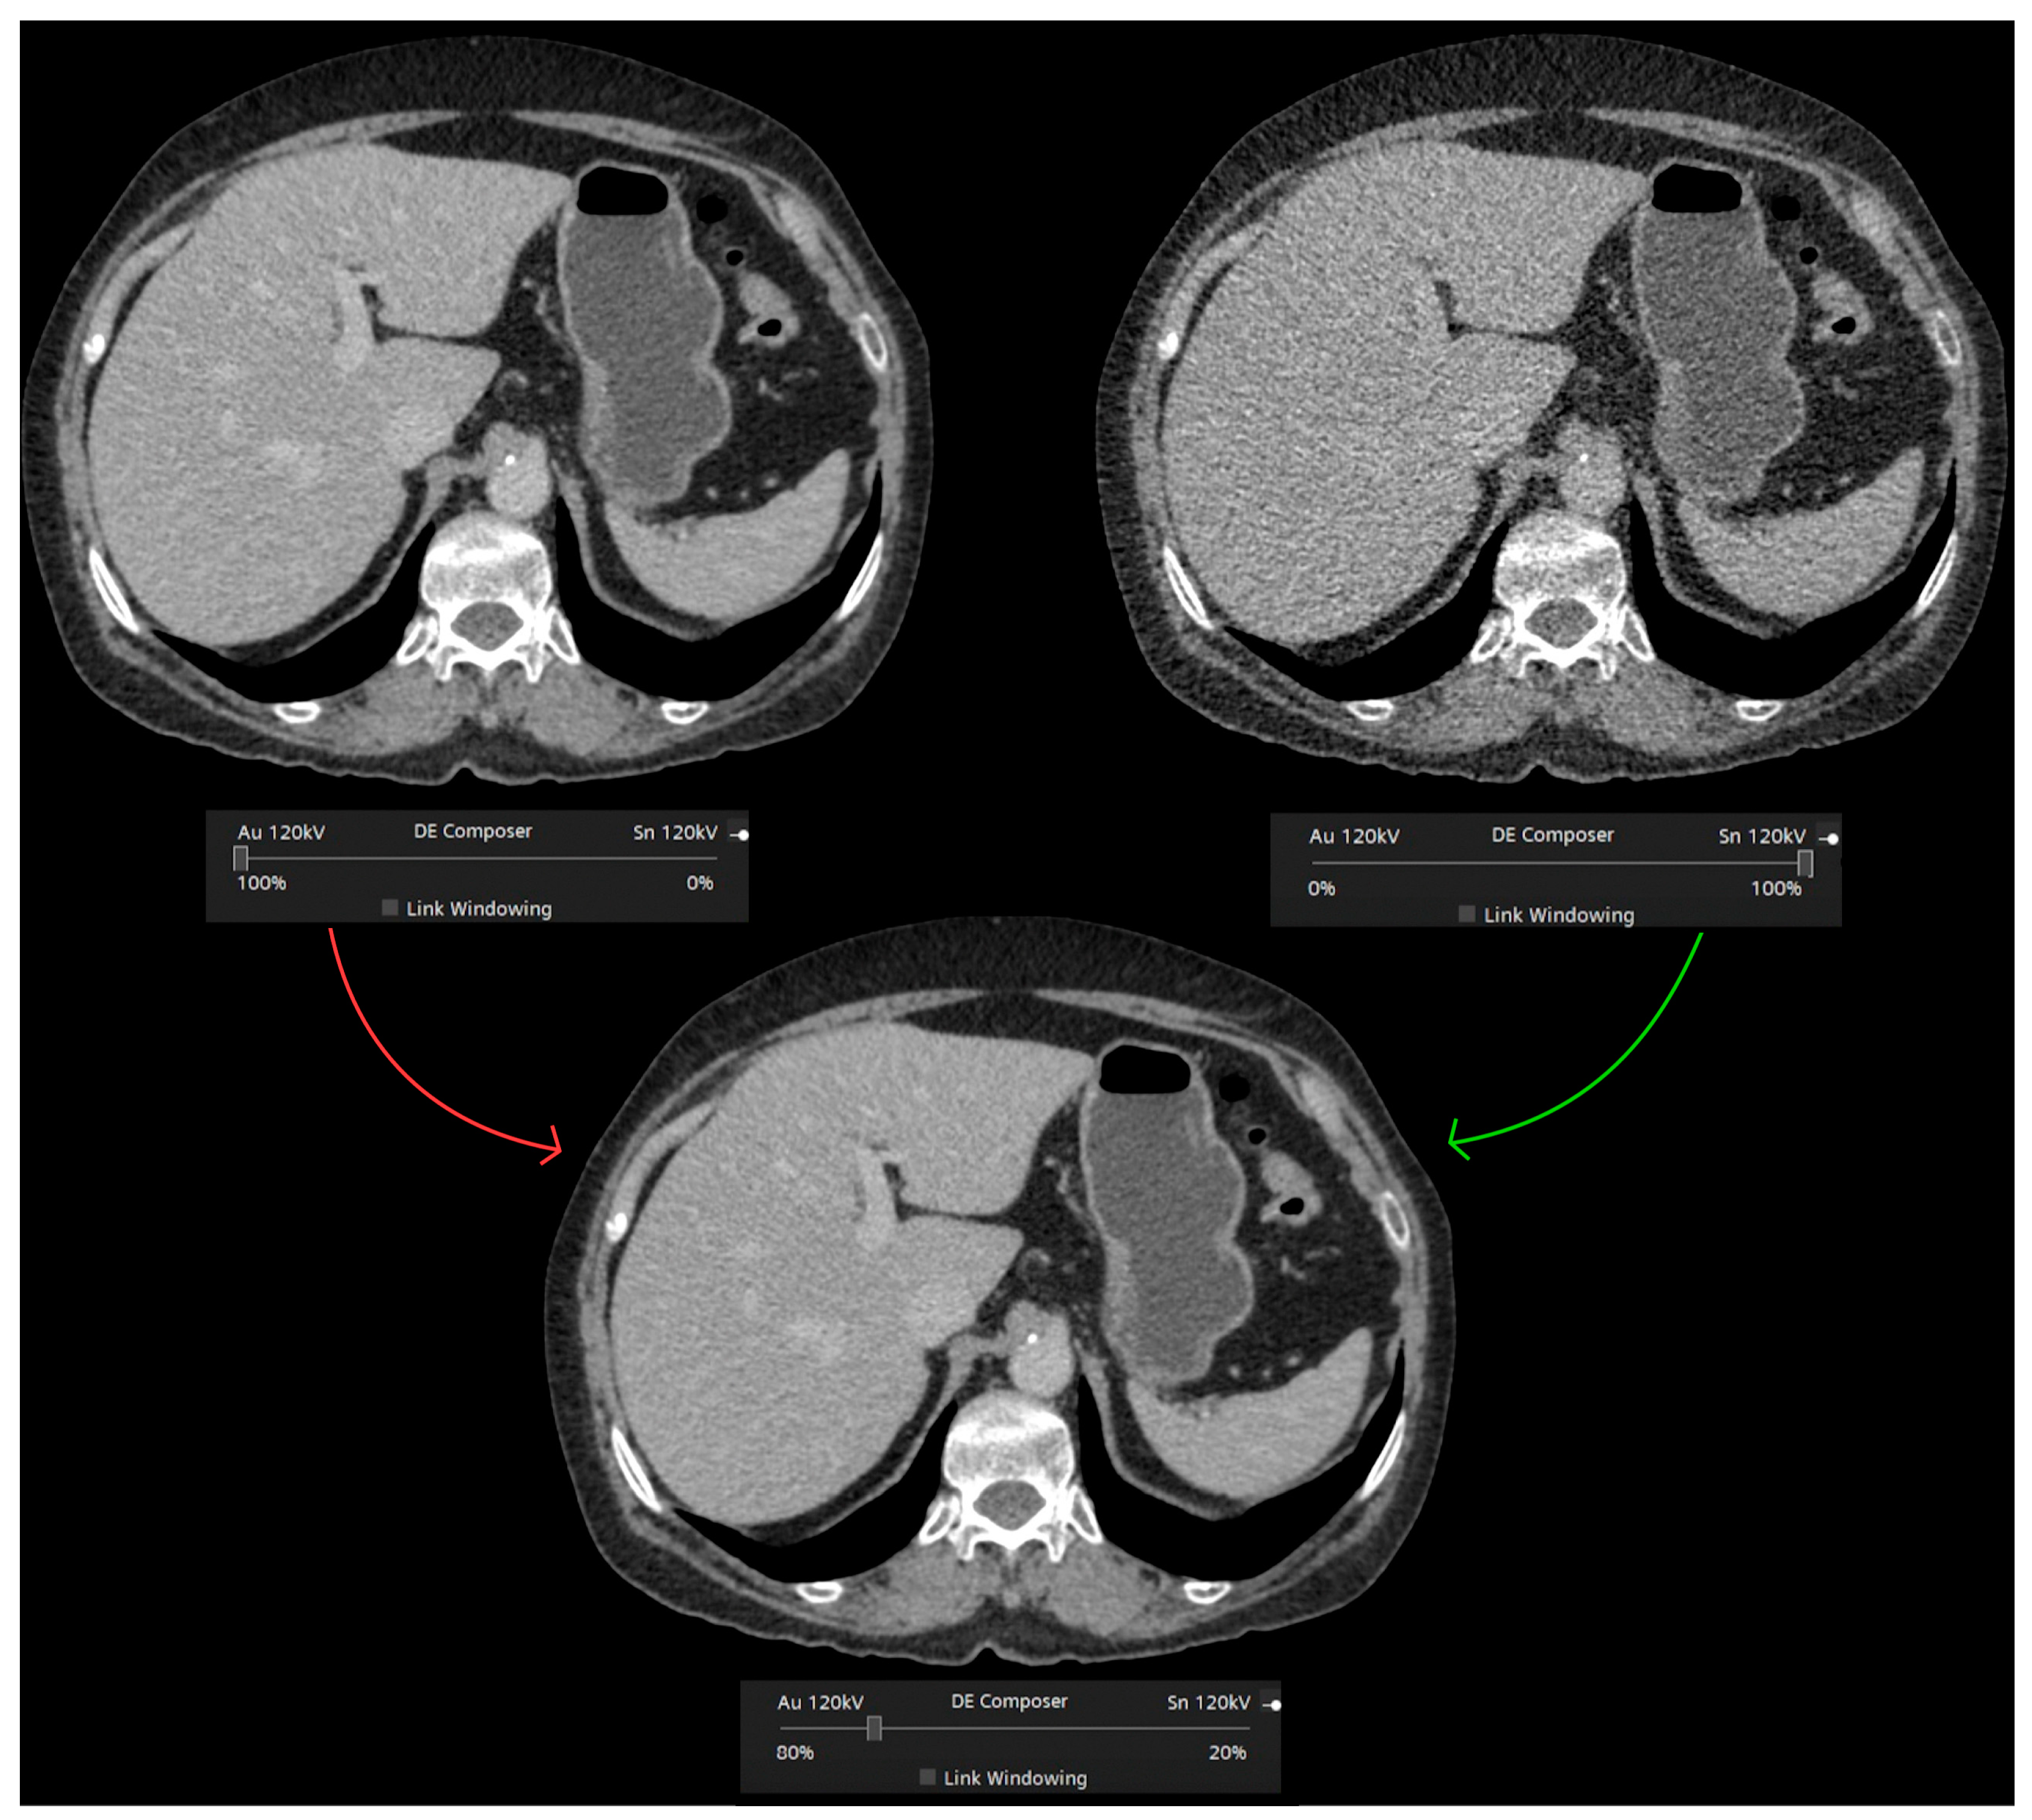

3.1. Postprocessing Techniques